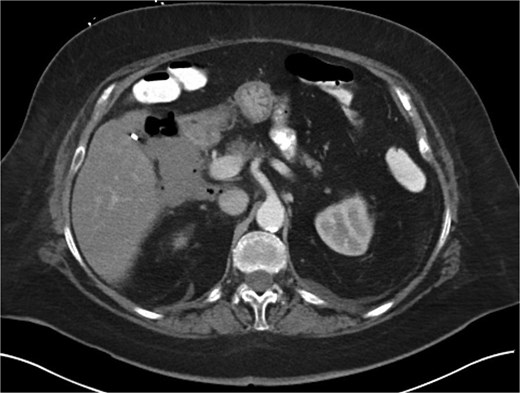

A 70-year-old woman with obesity, non-insulin-dependent diabetes, gastroesophageal reflux disease (GERD), cholecystectomy, and prior RYGB presented to the ED with acute chest and lower abdominal pain. The pain began 1 day earlier and initially responded to Ibuprofen, which she had been taking 4–6 times daily for musculoskeletal discomfort. Her pain worsened, radiating to her back, and was accompanied by belching and vomiting with dry heaving. She denied trauma or changes in bowel habits. Initial CT (Fig. 1) imaging showed a moderate hyperdense area around the duodenum, distension of the afferent limb and excluded stomach, and expected postoperative changes. She was admitted for conservative management. Four days later, a repeat CT (Fig. 2) was performed due to persistent symptoms, revealing free fluid in the intraperitoneal and retroperitoneal spaces, raising concern for duodenal perforation. She developed lethargy and diffuse abdominal tenderness and was taken to the operating room. Exploratory laparotomy with peritoneal washout, enterolysis, partial omentectomy was performed. It revealed two 1 cm posterolateral perforations of D3, which were repaired with an omental pedicle flap. The Roux limb was healthy, the jejunojejunostomy was dilated but patent, and the biliopancreatic limb was intact. Due to high vasopressor requirements, a temporary abdominal closure device was placed, and she was transferred to the surgical ICU. After stabilization, a second-look laparotomy was performed the next day to reinforce the duodenal closure, place a gastrostomy tube for drainage, and insert a J-tube for feeding (Figs 3 and 4). The abdominal wall was closed. On postoperative day 2, a CT with contrast showed extravasation from the duodenal repair site. Interventional radiology placed a transhepatic biliary drain to divert bile and support duodenal patch healing. Helicobacter pylori antigen was negative. Her condition improved, and she was started on an enteral and slow oral feeding regimen. However, at this juncture, the patient declined further treatment and requested comfort care measures.

Hospital Day 4 CT scan of the abdomen and pelvis A/P with oral and intravenous contrast demonstrating scattered pneumoperitoneum and free fluid by lateral duodenum.